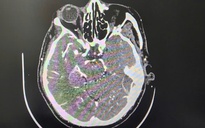

Nữ sinh được đưa đi cấp cứu tại Bệnh viện Hà Đông, sau đó chuyển tiếp lên Bệnh viện Bạch Mai trong tình trạng hôn mê. Kết quả chụp chiếu cho thấy bệnh nhân bị chảy máu não do vỡ dị dạng mạch máu bẩm sinh, một dạng đột quỵ não ở người trẻ.